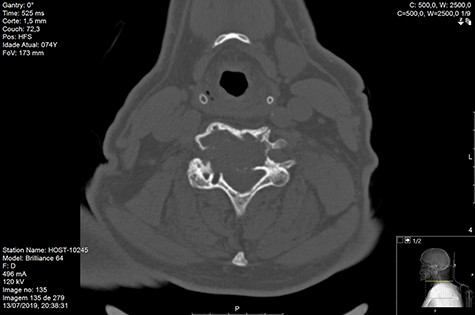

Computed tomography (CT) (Figs 1–3) and magnetic resonance imaging (MRI) (Figs 4–6) of the cervical spine were performed and revealed a lytic lesion involving most of C4, C5 and C6 vertebral bodies with bilateral extension to the posterior spinal elements of C4 and C5 and complete disruption of C4-C5 and C5-C6 intervertebral discs.

The Spinal Instability Neoplastic Score (SINS) [4, 6, 7] for assessing spinal instability from metastatic disease was used and the lesion was deemed unstable (SINS 13), with impending risk of increased neurological damage.

MRI and CT scans performed at 90 days post-radiation therapy showed an arrest of further progression of instability and resolution of the lytic lesion (Figs 7–13).